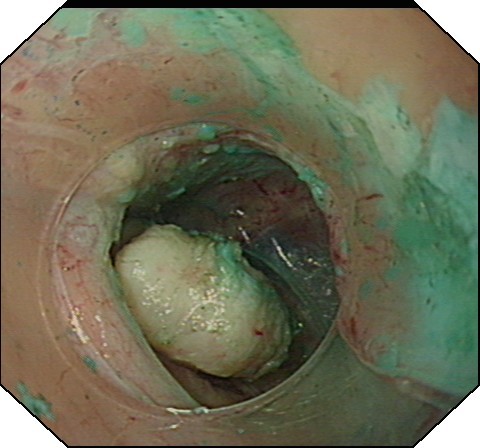

大家都知道,人体胃壁共有四层组织组成:由内到外分别为粘膜层、粘膜下层、肌层、浆膜层。胡妈妈的肿瘤就长在肌层,这是一种良性的胃肿瘤。通常,传统治疗方法一般建议外科手术治疗,开腹或开胸,有时还需要切除食管或者胃的一部分,创伤大,费用高,恢复期长。消化科吕宾教授对患者的检查资料进行仔细的研究分析,在获得患者的知情同意后,决定用国际内镜治疗的最新技术——经内镜粘膜下隧道肿瘤剥离术(STER)切除肿物。STER是通过在距肿瘤近口侧约3-5cm切开粘膜,建立粘膜下隧道(图1),逐步分离组织,显露肿瘤,再沿肿瘤包膜在内镜直视下剥离,完整剥离后取出肿瘤(图2),用金属夹关闭隧道口(图3)。

图3 钛夹关闭隧道口 图4 取出的瘤体